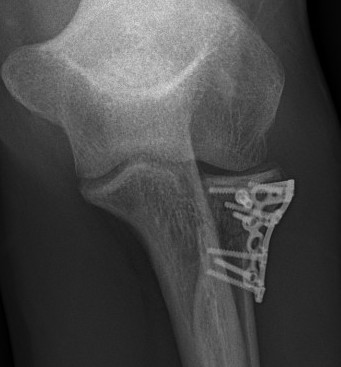

Radial Head Fixation

Indication

Significant fragment displacement

Reconstructable

Technique

- 2.5 or 3.5 headless compression screws

Complications

PIN injury

Intra-articular screws

Hardware failure

Heterotopic ossification

AVN

Non union

Radial head fragment nonunion

Results

Outcomes

- 56 patients with ORIF radial head

- 30 Mason 2, 26 Mason 3

- 13/14 patients with comminuted Mason 3 with > 3 fragments had poor outcome

- 15/15 patients with simple Mason 2 had good outcomes

- best results with 3 or fewer fragments